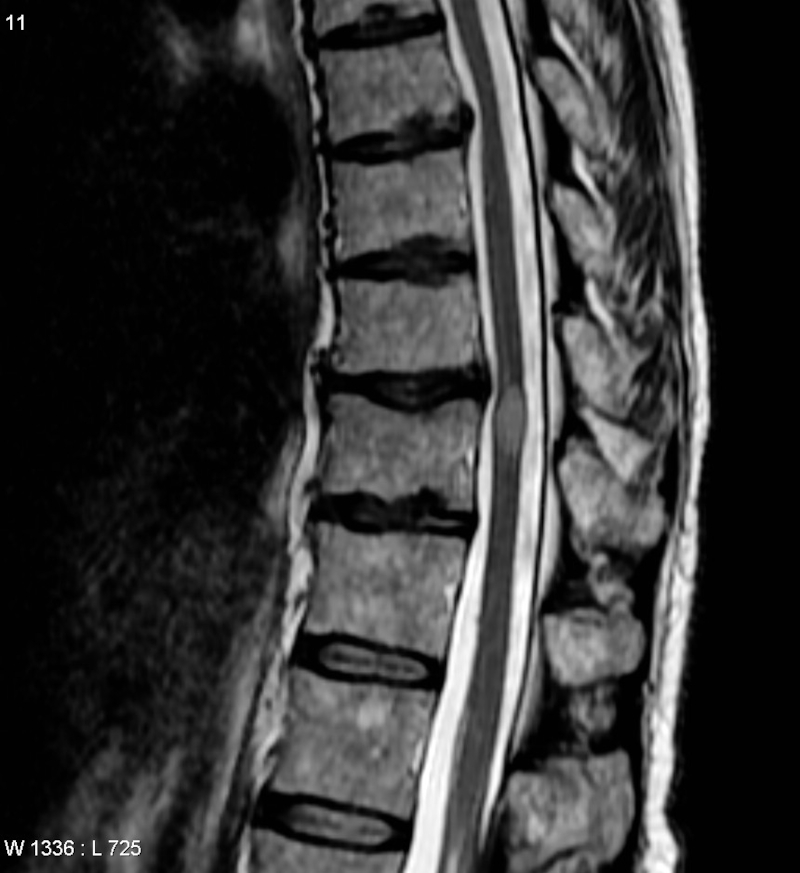

Lundi 22 novembre – Santé – Covid-19 et paralysie.

Des cas de paralysie à la suite d’une contamination par le Covid-19 sont rapportés dans plusieurs pays, relève un article scientifique publié en avril dernier par des praticiens américains et panaméens. Ils ont répertorié et étudié 43 cas d’inflammations de la moelle épinière (myélite transverse aiguë) dans 19 pays. Les autorités sanitaires suisses ont également constaté neuf cas de paralysie due à ce coronavirus. Pour la France, la Direction Générale de la Santé ne dispose pas d’un recensement de tels cas : « 196 articles sont recensés dans Pub Med [répertoire britannique d’articles médicaux internationaux], mais cela reste une pathologie rare », précise son porte-parole. Aucune enquête sur les séquelles durables ou permanentes est menée dans notre pays : « Nous n’avons pas connaissance d’une surveillance aussi fine au niveau national », précise la DGS. On ne sait donc pas combien de personnes sont concernées par une paralysie définitive ou partiellement réversible. Et concernant la reconnaissance des séquelles durables invalidantes au titre d’un handicap ouvrant droit aux prises en charges et aides prévues par la législation elle répond : « Il n’existe pas à ce jour d’Affection Longue Durée spécifique Covid mais les patients peuvent être reconnus en ALD de droit commun (hors liste). » Les victimes du coronavirus Covid-19 vivant avec des séquelles handicapantes permanentes ne peuvent être reconnues handicapées qu’au titre de ces séquelles.